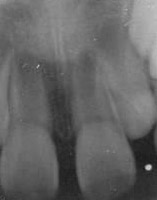

1. 과잉치

정상적인 치아의 개수보다 더 많은 치아가 자라나는 것을 말합니다.

유치열기에 발견되는 과잉치는 영구치의 맹출을 방해하는 요소가 되며

치아가 올바르게 배열될 공간이 부족하여 치아배열의 이상, 부정교합이 유발될 수 있습니다.